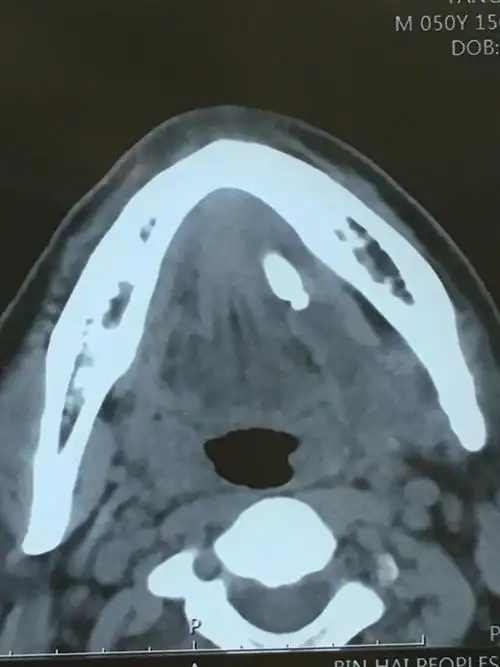

颌下腺巨大涎石